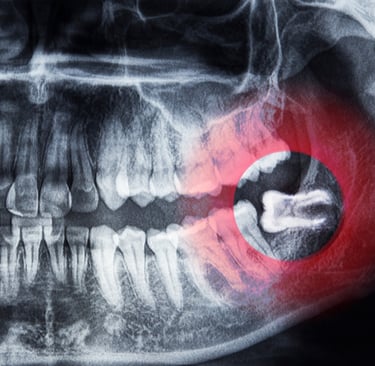

تشخيص ضرس العقل المطمور

تقييم شامل بالأشعة لتحديد درجة الانطمار والمخاطر المحتملة

يتم استخدام الأشعة البانورامية أو CBCT للحصول على صورة واضحة للعصب والعظم.

الخطوة الأولى ضرورية لتحديد ما إذا كان الضرس يحتاج قلعًا جراحيًا أو عاديًا.

• تحديد درجة الانطمار بشكل دقيق باستخدام الأشعة.

• تقييم المسافة بين الضرس والعصب لتقليل المخاطر.